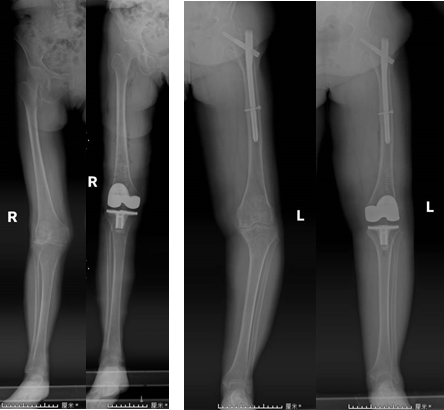

膝关节疼痛是困扰老年人常见的问题,而膝关节置换手术是治疗终末期膝关节退变的主要有效手段。近日,我院关节运动医学科康立新主任医师团队,利用全膝关节手术定位系统(iKAPS)完成两例复杂膝关节置换手术。该技术为膝关节畸形严重、股骨髓腔闭锁或者既往股骨近端手术有内植物的患者进行膝关节置换,提供了一种更加精准、有效的治疗方法。

术中使用类似麻将牌大小的下肢力线测量仪,配合医疗交互软件和配套工具,精准地测量出股骨远端和胫骨平台的截骨角度,辅助手术者进行个体化的精准截骨,恢复下肢力线。术中不需要打开股骨髓腔,比传统手术出血少、恢复快。全膝关节手术定位系统(iKPAS)可用于初次或复杂全膝关节置换手术,在不开髓的情况下实现膝关节力线的定位,尤其针对股骨骨折内固定物未取出的情况,优势更加明显。近年来,我院关节运动医学科在康立新主任医师的带领下,连续开展机器人辅助下髋、膝关节置换术,肘关节置换术,iKAPS辅助下复杂膝关节置换术等新技术,引领关节外科继续朝数字化、智能化、精准化、个性化发展。